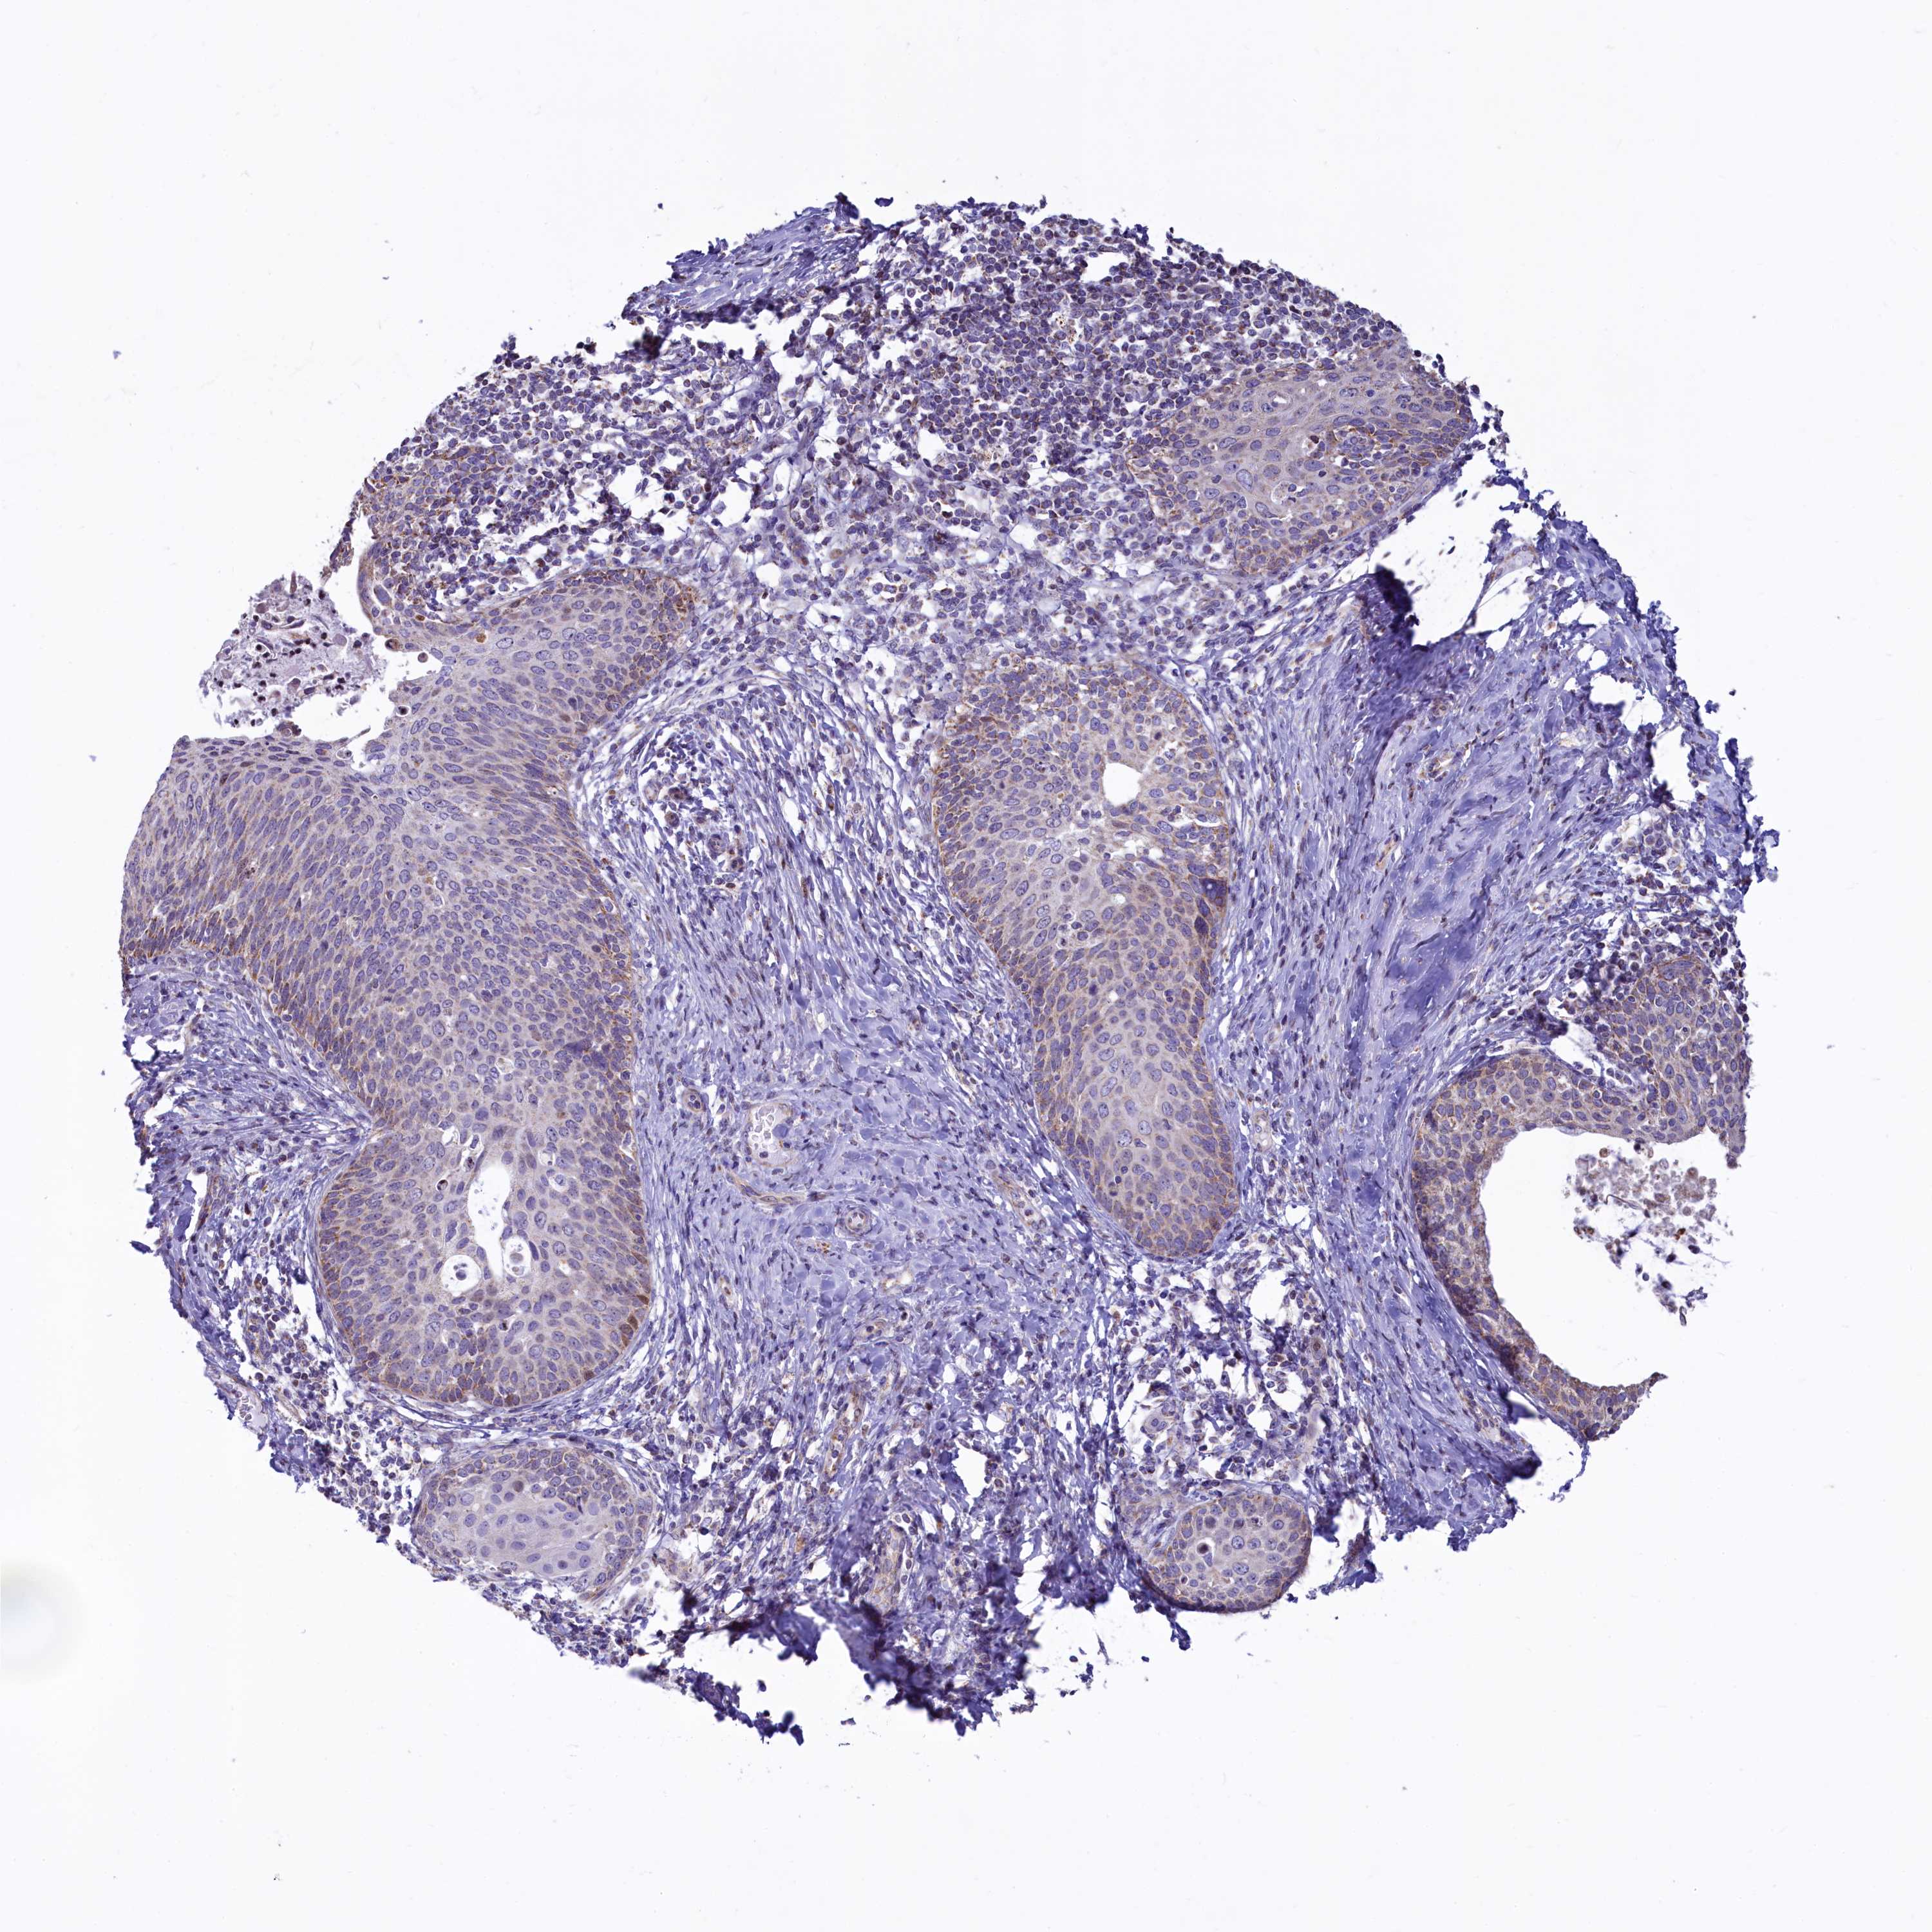

CERVICAL CANCER - Protein expressioni

A mouse-over function shows sample information and annotation data. Click on an image to view it in a full screen mode. Samples can be filtered based on level of antibody staining by selecting one or several of the following categories: high, medium, low and not detected. The assay and annotation is described here.

Note that samples used for immunohistochemistry by the Human Protein Atlas do not correspond to samples in the TCGA dataset.

Antibody stainingi

Antibody staining in the annotated cell types in the current human tissue is reported as not detected, low, medium, or high, based on conventional immunohistochemistry profiling in selected tissues. This score is based on the combination of the staining intensity and fraction of stained cells.

Each image is clickable and will lead to virtual microscopy that enables deeper exploration of all samples and also displays staining intensity scores, fraction scores and subcellular localization as well as patient and tissue information for each sample.

Antibody HPA040401

Antibody HPA043921

Staining

High

Medium

Low

Not detected

Intensity

Strong

Moderate

Weak

Negative

Quantity

>75%

75%-25%

<25%

None

Location

Nuclear

Cytoplasmic/membranous

Cytoplasmic/membranous,nuclear

Squamous cell carcinoma, NOS

Adenocarcinoma, NOS